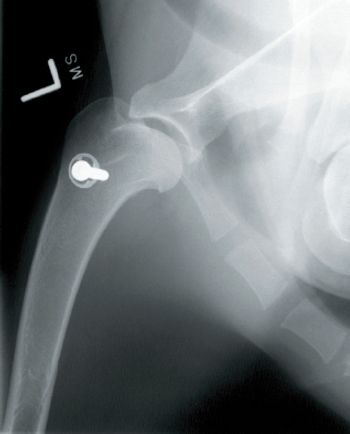

One of the most common injuries in sporting dogs involves the shoulder.

The most common indication for total joint replacement in the small animal is osteoarthritis or degenerative joint disease that is a cause of significant and frequent pain.